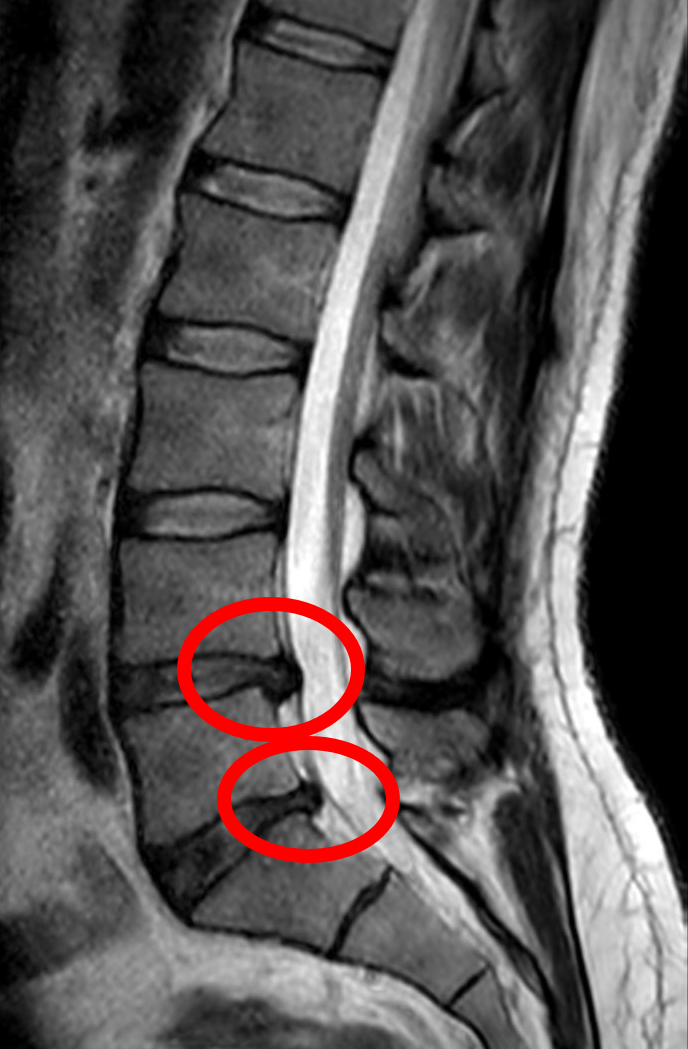

What is a Herniated Disc?

A herniated disc occurs when one of the discs in your spine slips out of place or ruptures, pressing on nearby nerves. This can lead to sharp pain, numbness, or tingling, especially in the back, neck, arms, or legs. Whether from an injury, poor posture, or age-related wear and tear, this common issue can drastically affect your quality of life.